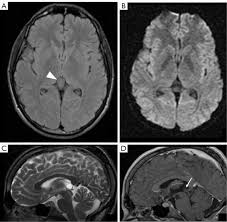

The diagnosis of pineal cyst is usually established by MRI with defined radiological criteria to distinguish benign pineal cyst from tumors of this area. A pineal cyst is usually only treated if it causes symptoms. In order to detect the presence of a cystic mass in the head magnetic resonance imaging is required.

Brain Magnetic Resonance Imaging Mri Of A 40 Year Old Patient Showing Download Scientific Diagram